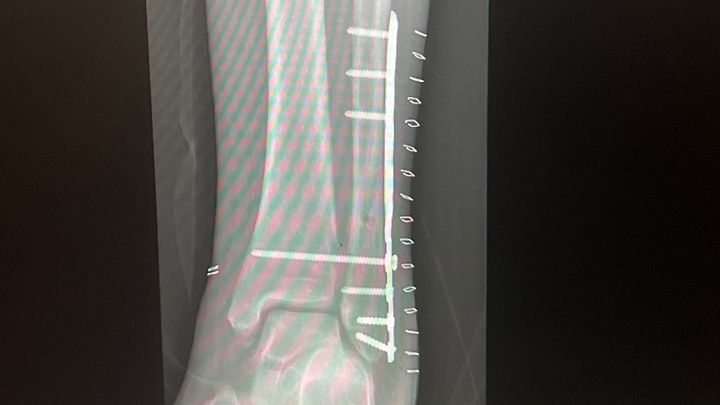

Hello, I’m Andre. I’m starting this for my mom; Gloria Michelle Freeman, she needs your help. She broke her leg back in November and had to have surgery. She wasn’t able to work till mid-January.

Now she has to have another procedure on her leg and doesn’t have the money. She doesn’t even have the money to get her regular monthly meds from the pharmacy. She doesn’t have money to pay her doctors appointments or physical therapy. She’s literally broke! Please find it in your hearts to help her out.